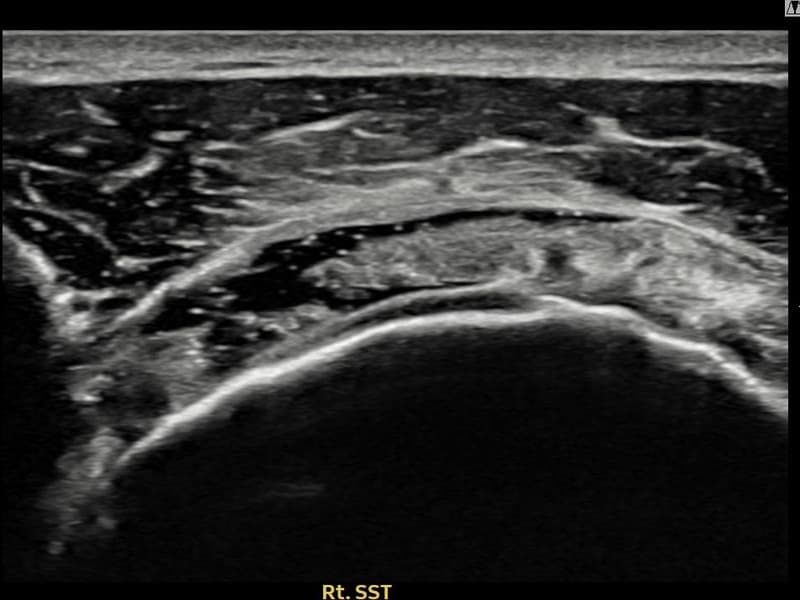

Before

시술 전 초음파 측정 결과 파열 크기는 16mm × 5mm (힘줄 두께의 약 75% 결손)로 확인되었습니다. 시술 전 초음파에서 우측 극상근건 관절면측의 광범위한 에코 단절과 힘줄 두께의 심각한 감소가 확인되었습니다. 시술 후 초음파에서 광범위 파열 부위에 재생 조직이 형성되고 힘줄 연속성이 안정적으로 회복된 것이 관찰되었습니다.

60대 초반 남성 환자분으로, 타 병원 두 곳에서 전층파열 직전 단계라며 수술을 권유받으셨으나 수술 후 재활 기간과 합병증 위험 때문에 비수술 치료를 원해 내원하셨습니다. 정밀 초음파 검사에서 관절면측 극상근건의 광범위한 부분파열이 확인되었으며, 힘줄 두께가 건측 대비 75% 이상 감소된 상태였습니다. 파열 범위가 넓어 일반적인 주사 치료나 물리치료로는 구조적 회복이 어렵다고 판단하였으며, 초음파 유도 하 축소봉합술을 시행하였습니다. 시술 후 보조기 착용 6주를 유지하며 단계적 재활을 진행하였고, 11주 후 추적 초음파에서 재생 조직 형성과 힘줄 연속성 회복이 확인되어 수술 없이 안정적인 치료 결과를 얻으셨습니다.